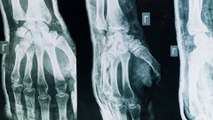

Artrite e artrosi sono tra le più diffuse malattie articolari, due condizioni che condividono

alcuni sintomi ma differiscono per causa evoluzione e trattamento. Con il termine

artrite si intende un gruppo di malattie infiammatorie delle articolazioni. Può avere

origine autoimmune, infettiva o essere legata ad altre malattie sistemiche. Una delle forme

più studiate è l'artrite reumatoide che si manifesta con infiammazione persistente,

dolore e gonfiore e può colpire più articolazioni in modo simmetrico. In Italia si stima che

l'artrite reumatoide colpisca circa 400.000 persone. Al contrario l'artrosi è una malattia

degenerativa caratterizzata dall'usura della cartilagine articolare, alterazioni della

struttura ossea sotto cartilaginea e cambiamenti delle cellule articolari. È la forma più comune

di malattia articolare. I principali fattori di rischio sono l'età, il sovrappeso, il

sovraccarico articolare, traumi pregressi, predisposizioni genetiche. Marco Klinger ha

sveglio. La diagnosi di artrosi tuttora si fa con

la semplice radiografia. Andare a vedere quello che è il consumo della cartilagine

del capo di uno dei due capi ossei porta un avvicinamento delle due osse all'interno

dell'articolazione. Per quanto riguarda l'artrosi fare una diagnosi precoce non